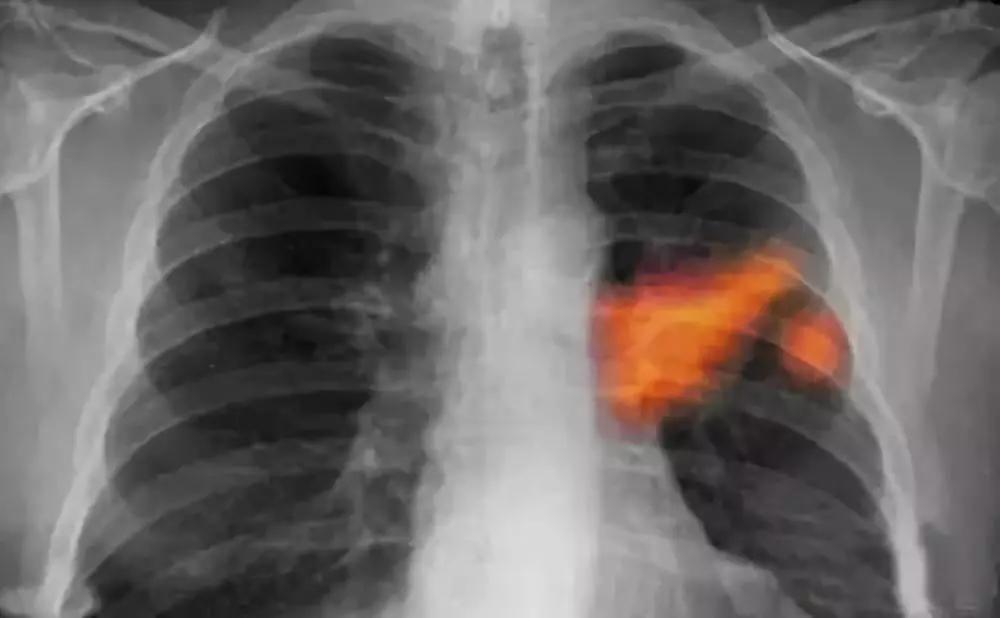

肺癌

多发生在40岁以上男性,长期吸烟者,常有痰中带血,刺激性咳嗽。胸部X线检查肺部有块影或阻塞性肺炎。痰脱落细胞或纤维支气管镜检查可明确诊断。